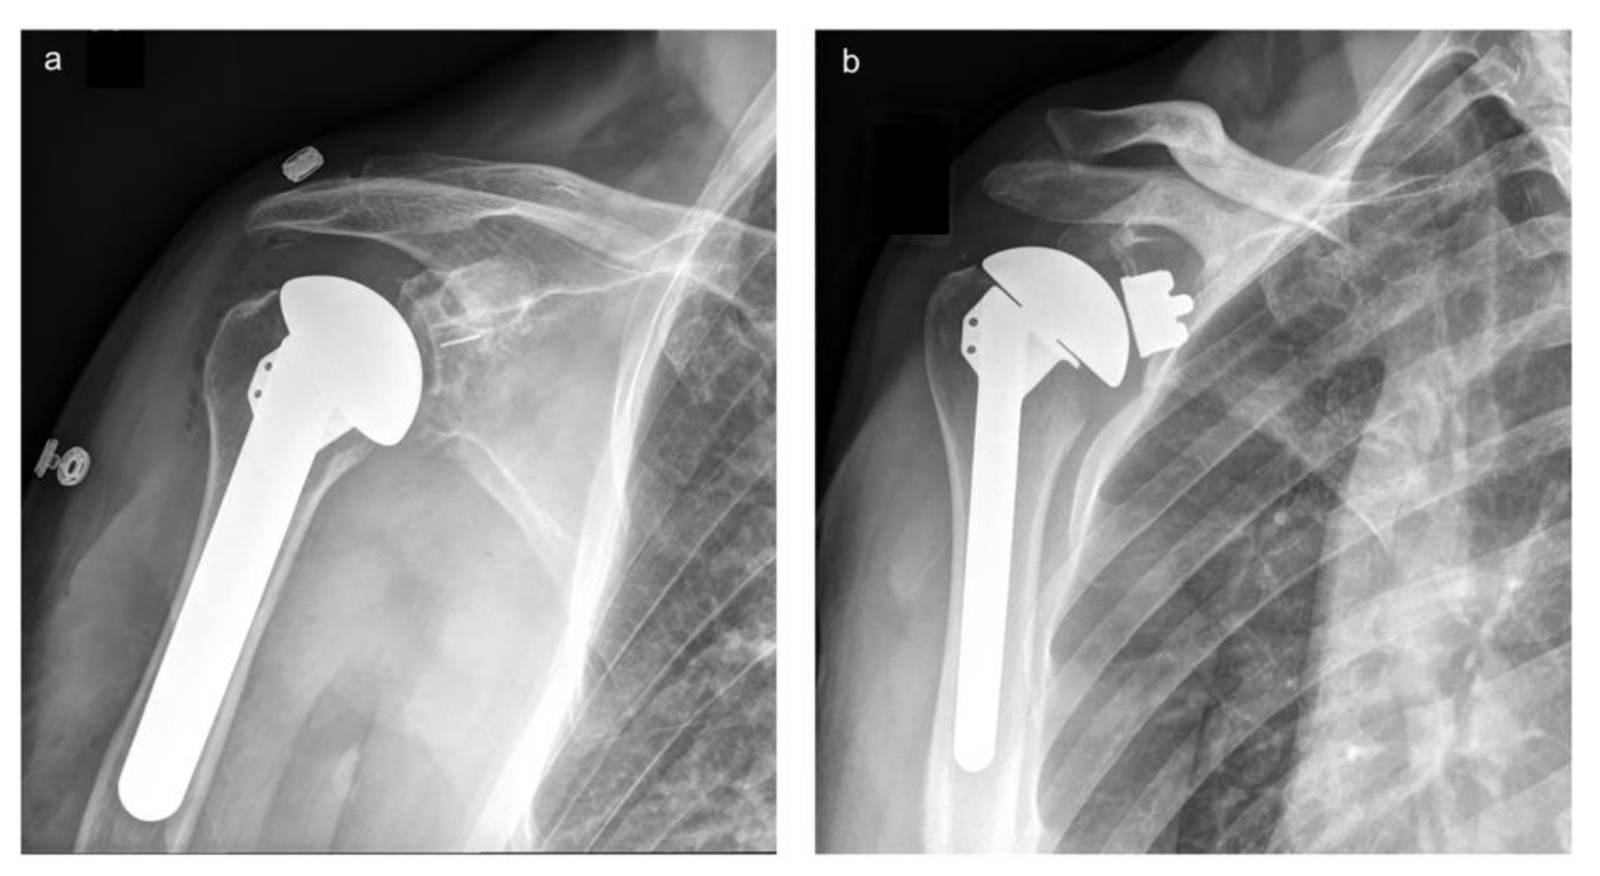

Total shoulder arthroplasty, also known as total shoulder replacement, is a surgical procedure that replaces both the damaged ball (humeral head) and socket (glenoid) of the shoulder joint with artificial components. At our Delhi orthopedic center, our experienced surgeons use advanced implants and precision techniques to restore joint mobility, eliminate pain, and help patients return to their normal activities.

This procedure is performed to treat severe shoulder arthritis, joint degeneration, or injury when non-surgical treatments are no longer effective. The damaged parts of the shoulder joint are replaced with smooth, durable prosthetic components that mimic the natural anatomy of the shoulder.